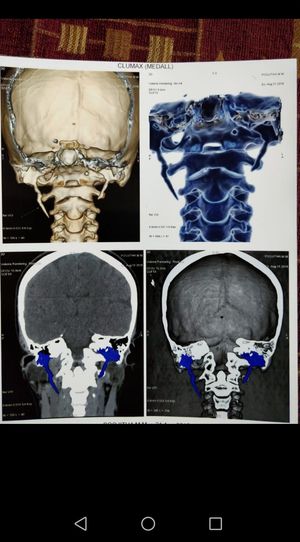

ELONGATED STYLOID PROCESS

ELONGATION STYLOID PROCESS